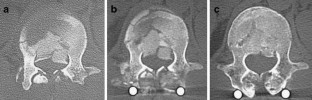

The purpose of this study is to investigate the clinical outcome of posterior stabilization without decompression for thoracolumbar burst fractures. Thirty-one consecutive cases of thoracolumbar fractures involving T11–L2 stabilized by a pedicle screw system were reviewed. Neither reduction of the height of a fractured body nor any decompression procedure was added during surgery. Twenty-two patients had incomplete paraplegia; one patient had complete paraplegia. Neurological recovery and remodeling of the spinal canal were evaluated. Neurological status was evaluated at the time of injury, just before and after surgery, and at final follow-up. The degree of spinal canal compromise was assessed using axial CT scan images. The duration of follow-up averaged 39.6 months. The mean spinal canal compromise at the time of injury was 41.6%, and no significant correlation was observed between the degree of canal compromise and the severity of the neurological deficit. Within 2–3 weeks, spinal canal remodeling had started in all patients whose spinal canal compromise was more than 30%, and canal compromise had decreased significantly 3–4 weeks after injury. Seventeen of 22 patients with incomplete paraplegia had already shown partial neurological recovery even before surgery. At the final follow-up, all patients with incomplete paraplegia had improved by at least one modified Frankel grade. This study suggests that the effect of decompressing thoracolumbar fractures with neurological deficits remains unclear and questions the need to operate simply to remove retropulsed bone fragments. Posterior stabilization without decompression should constitute appropriate surgical treatment for these fractures.

Fig. 3